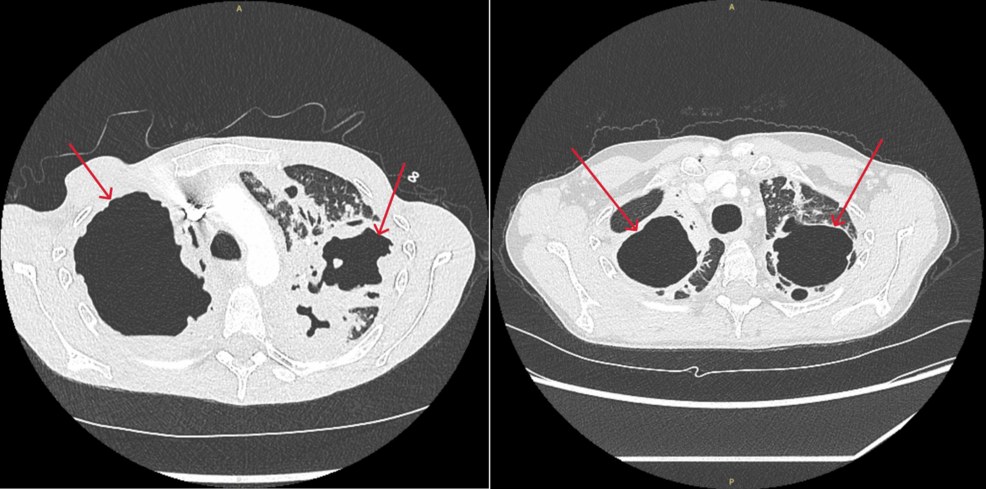

Invasive Pulmonary Aspergillosis Presenting as a Giant Abscess in a Post-tuberculosis Destroyed Lung: A Case Report Cureus